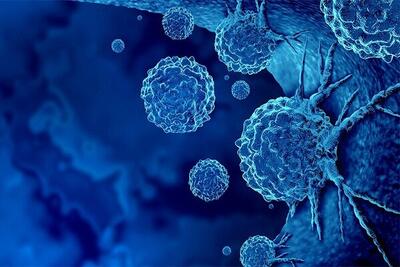

شرکت مایکروسافت بهعنوان یکی از غولهای فناوری دنیا با کمک هوش مصنوعی، ابزاری برای تصاویر آنالیز دقیق تصاویر پزشکی ارائه کرده است. اهمیت تشخیص درست جزئیات تومور و سلولهای سرطانی در تشخیص این بیماری و یا درمانهای پیشرفته مانند ایمونوتراپی، اهمیت زیادی دارد.